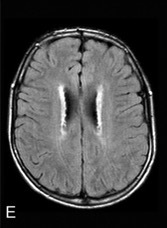

图 11 第一例患者 34 岁时的 MRI 提示右顶叶 FLAIR[A] 高信号和 DWI[C] 弥散受限;36 岁的 MRI 提示 FLAIR[B] 和 DWI[D] 上病灶进展;第二例患者 48 岁时的 MRI 提示 FLAIR[E] 和 T2WI[F~G] 上广泛的白质高信号